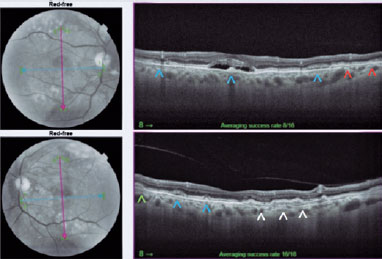

Fundus autofluorescence (FAF) showed hypoautofluorescent lines starting from the optic disc in both eyes and small, sparse hyperautofluorescent lesions in the posterior pole (Figure 1). Optical coherence tomography (OCT) of the right eye detected a subfoveal hyporeflective space containing hyperreflective materials. In the left eye, a double-layer sign was seen, but without signs of exudation (Figure 2).

Multimodal evaluation of the posterior segment confirmed that the case was an association of two ophthalmological diseases, AS and adult-onset foveomacular vitelliform dystrophy of the multifocal type. The concomitant presence of AS and PD has been established in the literature and commonly described in patients with pseudoxanthoma elasticum(1). This diagnosis was excluded for our patient by the medical clinic and dermatology teams. This PD subtype presents with central or paracentral subretinal deposits, yellowish and round, which appear as hyperautofluorescent lesions in the FAF and hyperreflective lesions between the retinal pigment epithelium (RPE) and inner segment/outer segment (IS/OS) layer of photoreceptors in the OCT(3,4). Druses, large or small, are an important differential diagnosis of vitelliform lesions, but they are located between the RPE and Bruch’s membrane(4,5).

The patient had two entities that were potentially progressing to CNV. In the OCT of the right eye, changes observed may lead to the erroneous diagnosis of active CNV. Through multimodal analysis using OCT-A and FFA, the changes indicated a resorbing vitelliform deposit. Owing to the possible emergence of a neovascular membrane, the patient was followed with serial tests.